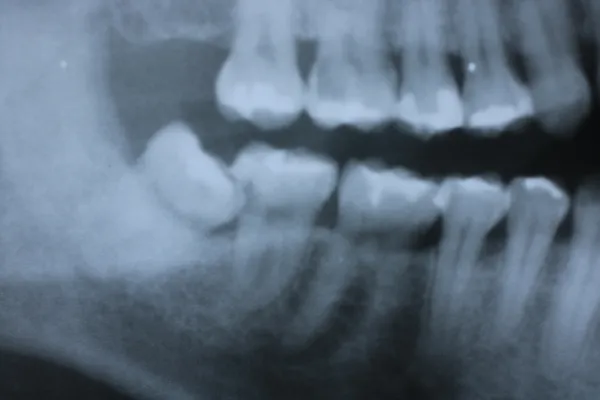

7親知らず

Case7